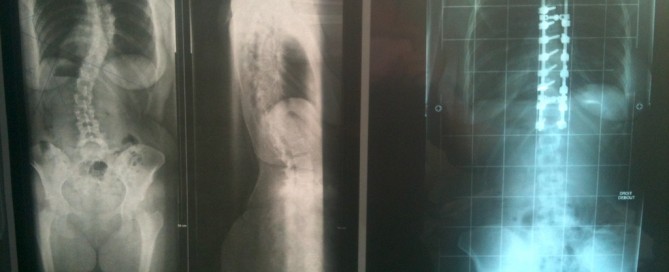

Mais littéralement ! 🙂 Le 2 avril dernier, ça a fait 6 ans que j’ai été opérée du dos. Je l’évoque souvent, mais je n’en ai jamais parlé en détail. Dans une story Instagram, je vous demandais récemment si c’est un sujet que vous vouliez que j’aborde sur le blog, et les réponses ont été [...]